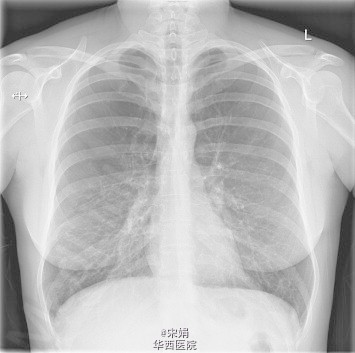

28岁的COPD,你遇到过吗?

COPD一般很少在年轻人中发生,几乎不在40岁以下的人群中诊断。此患者是 一个28岁的年轻女性,咳嗽、呼吸困难进行性加重2-3年,伴喘息、胸闷、夜间咳嗽,活动耐量低(MRC4分)。12年吸烟史,每天20支(!!),有甲减病史。家族中母亲和外婆都有COPD。治疗方面很遗憾,患者发病后仍持续吸烟,治疗效果不明显。